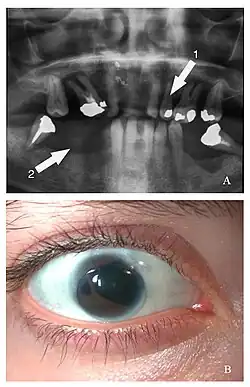

![]() Cechy fenotypowe zespołu Axenfelda i Riegera u 21-letniej pacjentki. Na pantomogramie zaznaczono hipodoncję (strzałka 1) i obszar hipoplazji szczęki (strzałka 2); na zdjęciu niżej widać dodatkowy otwór źreniczny (polycoria) | |

Zespół Axenfelda-Riegera (ang. Axenfeld-Rieger syndrome, ARS) – zespół wad wrodzonych, charakteryzujący się występowaniem obustronnych wad przedniego odcinka oka skojarzonych z wadami rozwojowymi zębów, środkowej części twarzy i jamy brzusznej. Większość przypadków zespołu wiąże się z mutacjami genów PITX2 lub FOXC1. Zespół opisali niezależnie od siebie Theodor Axenfeld i Herwigh Rieger.

- w zespole Riegera obok obustronnych wad przedniego odcinka oka stwierdza się dodatkowo wady zębów, takie jak mikrodoncja, hipodoncja, anodoncja albo hipoplazja szczęki, cechy dysmorficzne twarzy: szeroki grzbiet nosa, telekantus, hiperteloryzm oczny.